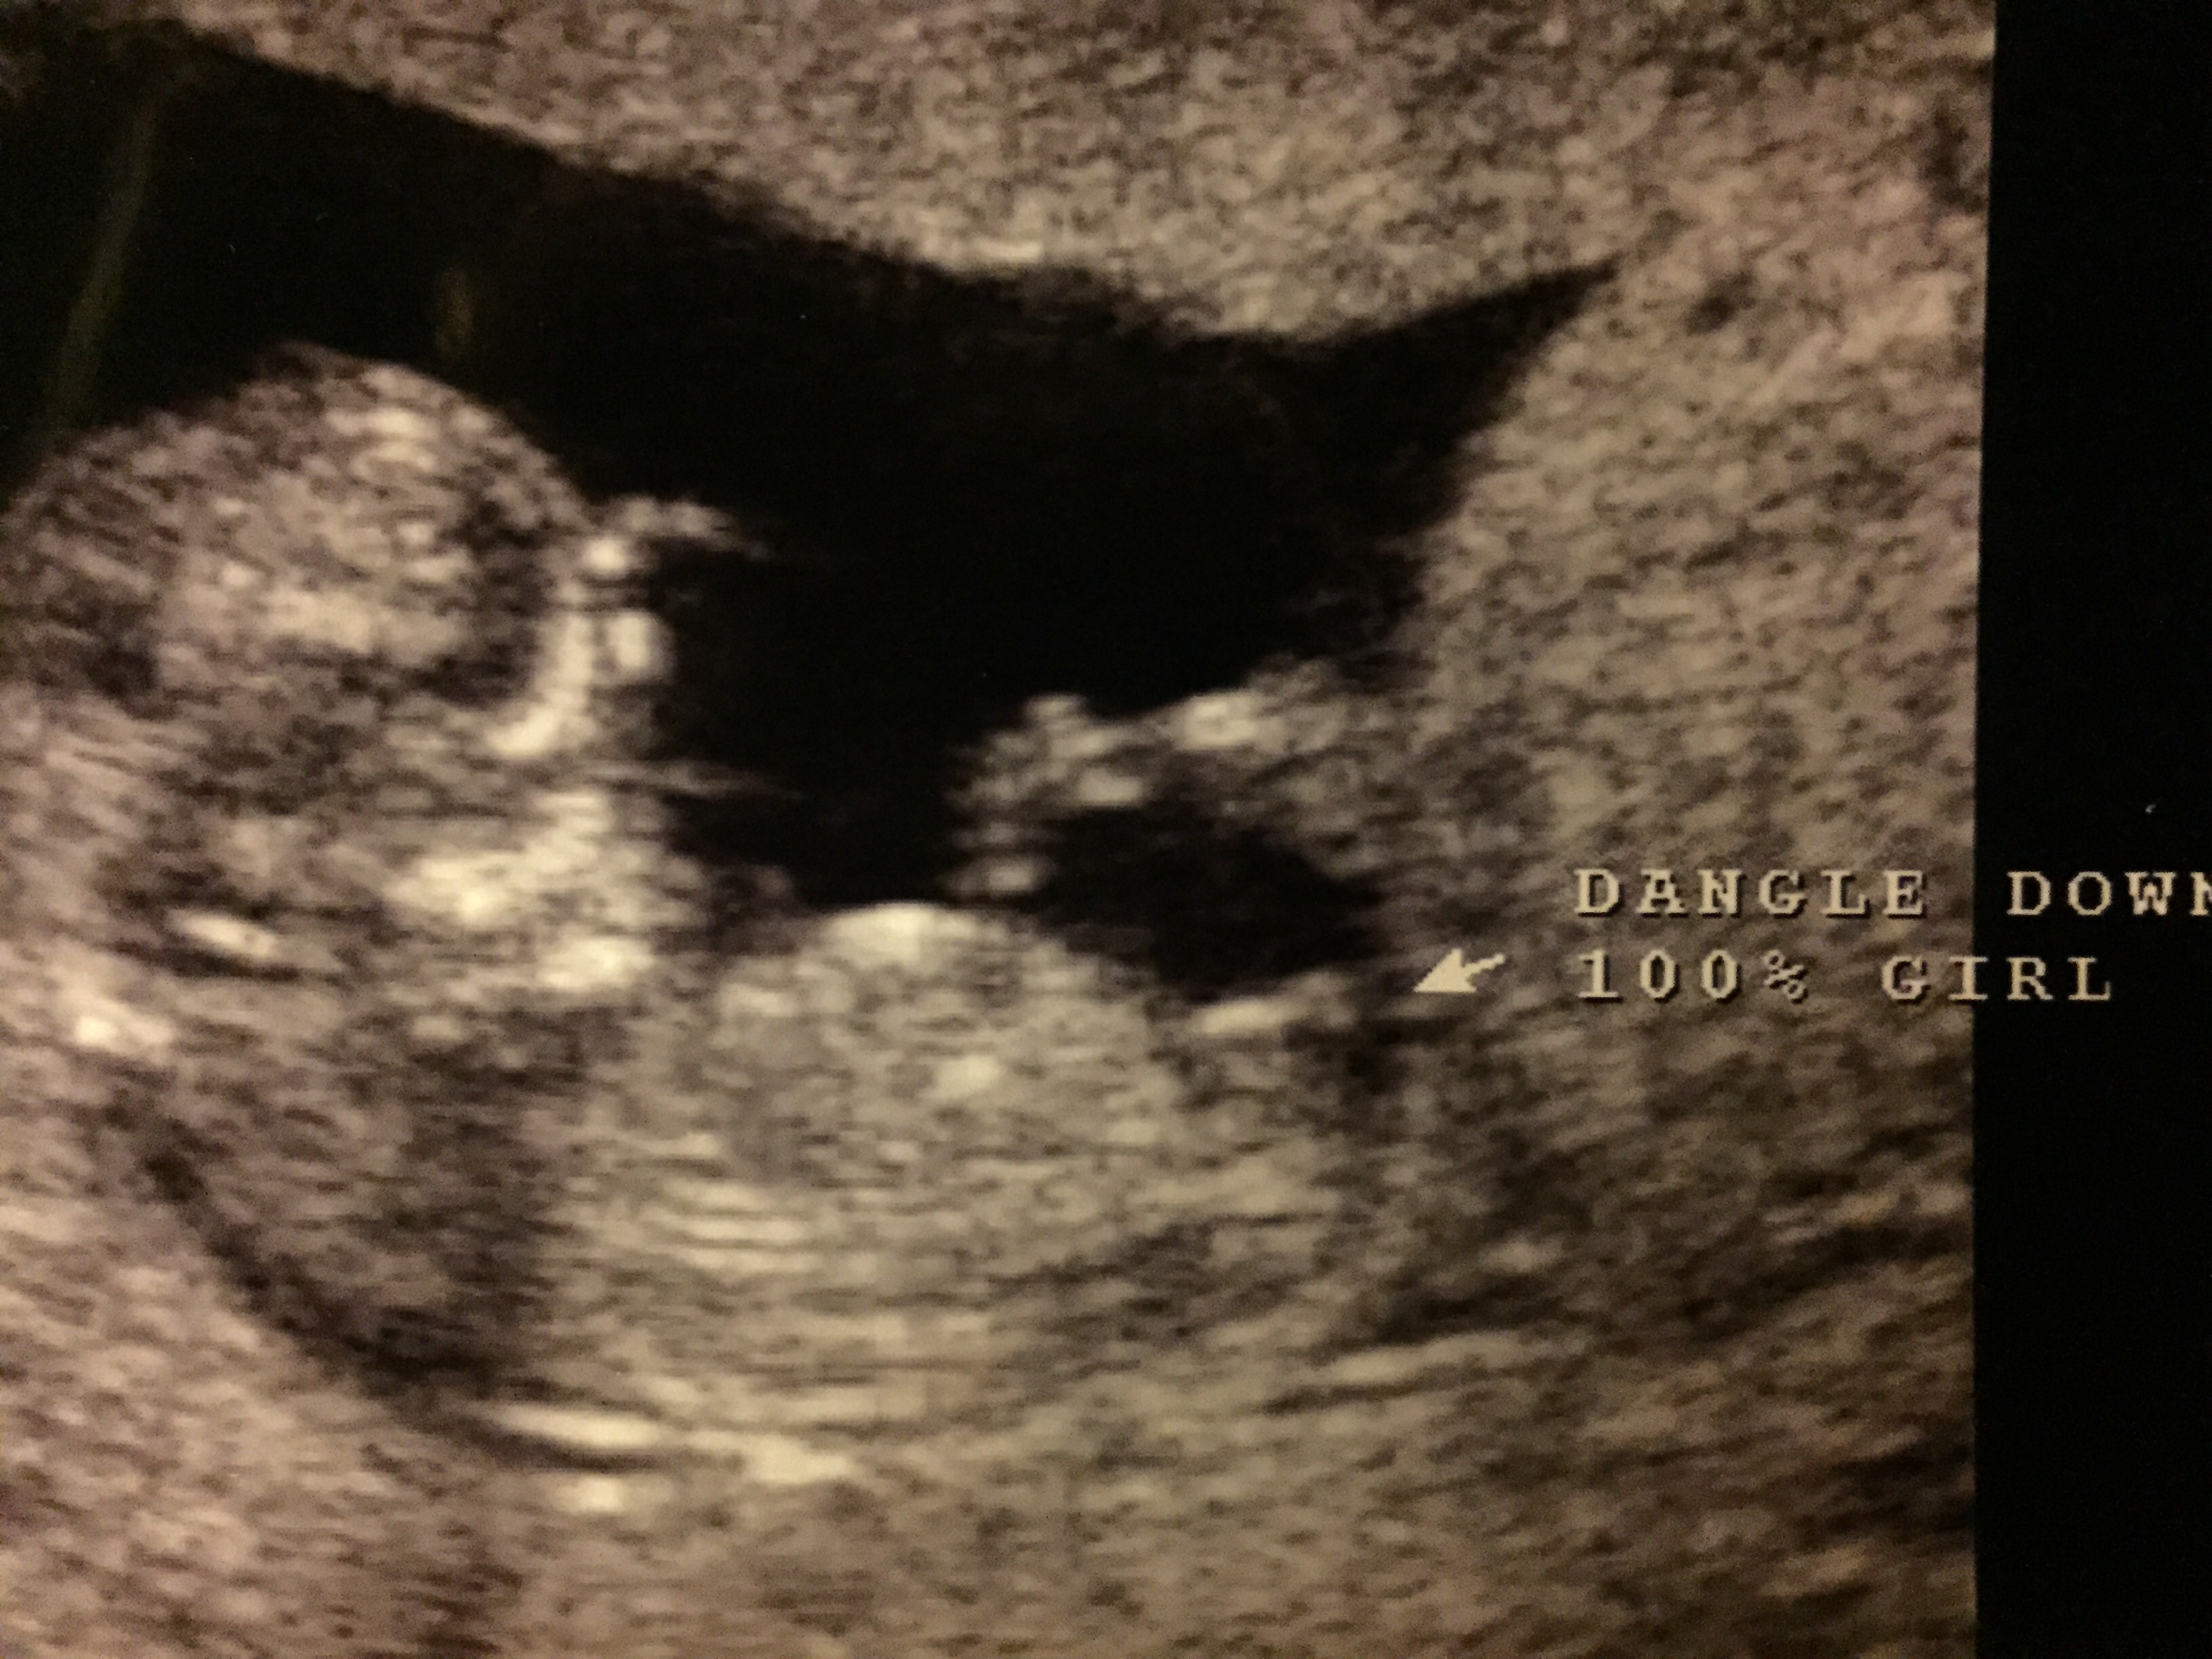

Team Pink

Re: Team Pink